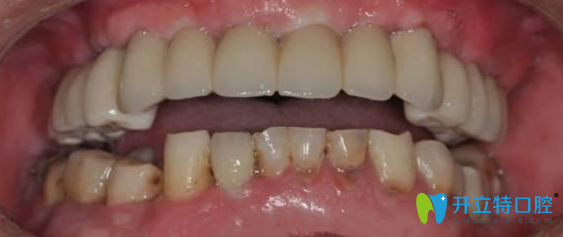

張叔戴上牙冠后:

經(jīng)過(guò)6個(gè)月的恢復(fù)期后,田醫(yī)生檢查確認(rèn),牙槽骨和種植體緊密結(jié)合,為他裝上了牙冠。完成種植牙全過(guò)程,張叔真是人老心不老呀!裝上牙冠后,急著照鏡子看看南京金臺(tái)口腔牙齒種植后的效果怎么樣?看著一排整齊的牙齒,激動(dòng)的說(shuō),原來(lái)我還可以這么帥,晚上一定要去飯店吃羊肉火鍋,過(guò)把癮。